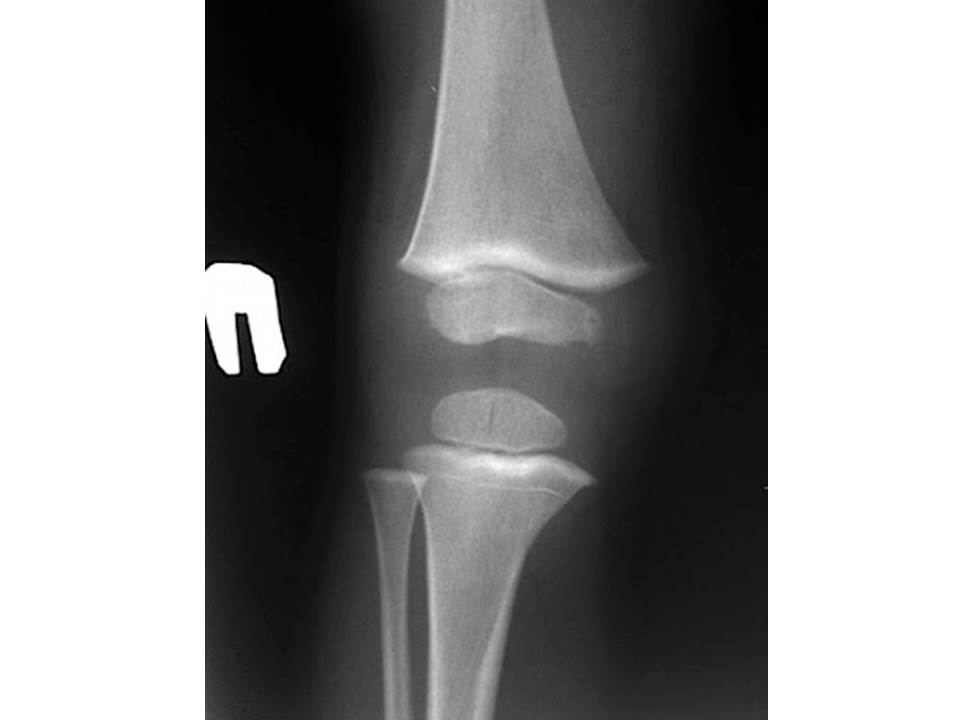

На фото  - рентгенограма колінного суглоба (пряма проекція).

Це рентгенограма дорослої людини чи дитини?

Обгрунтуйте свою відповідь. Для цього використайте знання з теми 10 Розділу ІІІ.